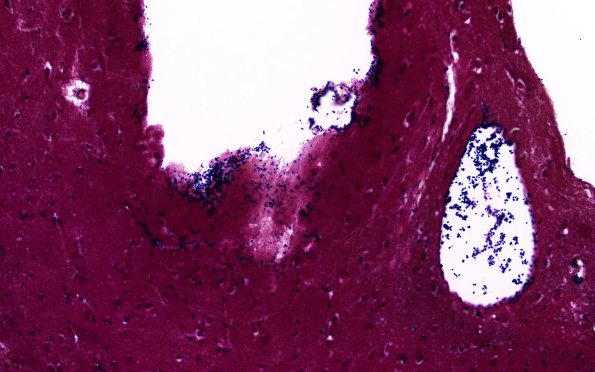

Washington University Experience | BASIC PROCESSES | Artifacts | Artifact - Swiss Cheese Brain | 34C2A Swiss Cheese Brain (Case 12) Gram 40X 6

34C2A-C Bacteria are found in the vasculature and at the margins of the cysts. (Gram)